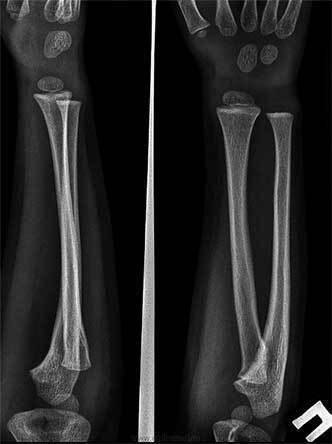

Очевидно, что немаловажную роль сыграл и случай с ребенком с диагнозом радиоульнарный синостоз. Это аномалия развития возникает в результате нарушения процесса внутриутробного развития малыша, когда нарушается процесс апоптоза – то есть процесс разделения лучевой и локтевой костей.

На иллюстрации справа пример синостоза сверху и нормы снизу: